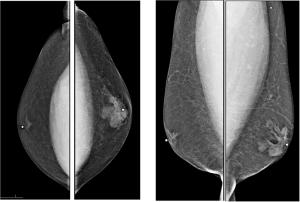

A 55-year-old female found to have a cardiac mass during evaluation of dizziness. Cardiac CT showed lesion of soft tissue density confined in right atrium.